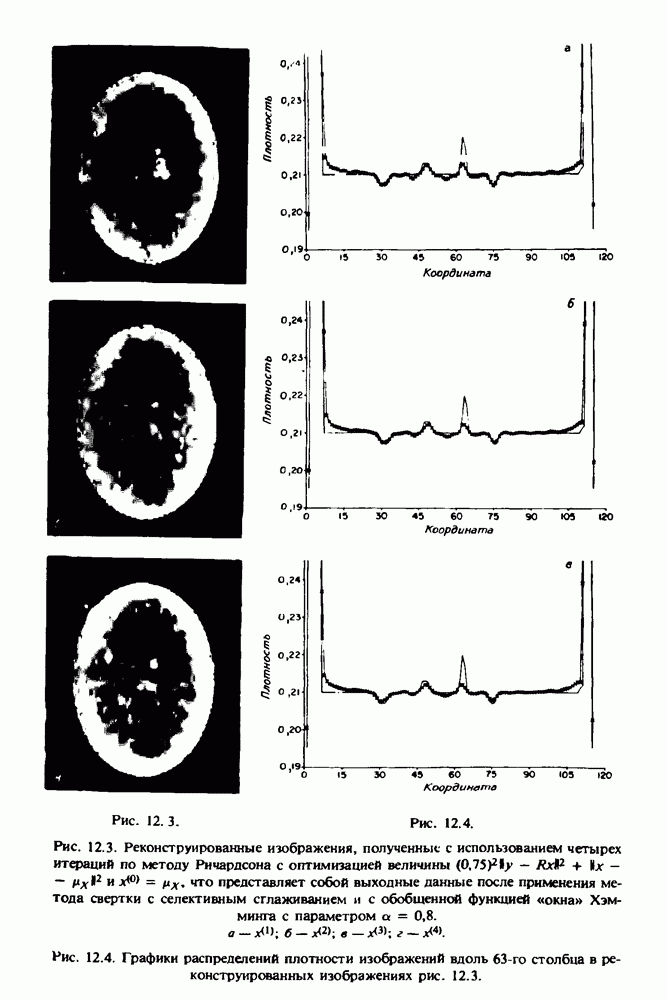

Проблема отображения срезов толщиной 1,5 мм состоит в том, что для «заполнения» элементарными объемами значительной части спинного мозга требуется большое число срезов. Один и тот же пациент должен быть просканирован 10 раз для получения смежных срезов толщиной 5 мм, а затем по этим срезам необходимо формировать трехмерный массив, содержащий в данном случае элементарных объемов размером 0,8 х 0,8 х 0,8 мм. Вид слоев, изображенный на рис. 15.10, приблизительно соответствует изображению рис. 15.9, хотя между ними имеется одно существенное отличие: числа Хаунсфилда, связанные с костной спикулой, на рис. 15.10 оказываются ниже настолько, что на правом изображении

Рис. 15.9. (см. скан) Два последовательных среза толщиной 0,8 мм, вычисленных путем интерполяции данных по срезам толщиной 1,5 мм. — изображения, соответствующие приведенному в области из 96 х 96 элементов на рис. 15.8; б - совокупность элементов изображения с «высокими» значениями чисел Хаунсфилда показана светлой, причем выбор высоких значений был сделан для выделения костных тканей.

рис. 15.10,б спикула не выглядит полностью отделенной от спинного мозга. Это изображение — иллюстрация возникающего эффекта частичного заполнения, описанного в разд. 3.3. Изображение спикулы настолько тонкое, что не может заполнить полностью элементарный объем в срезах толщиной 5 мм, поэтому числа Хаунсфилда в пределах среза неточно характеризуют коэффициент линейного ослабления рентгеновского излучения в костных тканях спикулы. Напротив, срезы толщиной 1,5 мм оказываются достаточно тонкими и позволяют получить точные значения чисел Хаунсфилда (рис. 15.9); при этом спикула на изображении идентифицируется достаточно точно.

Это явление иллюстрируется также рис. 15.11 и 15.12, где левые изображения получены по серии из 10 срезов толщиной 5 мм, а правые — по серии из 8 срезов толщиной 1,5 мм. На рис. 15.11,а и 15.12,а за основу взяты изображения рис. 15.8 — 15.10, в которых фрагмент из 96 х 96 элементов изображения использовался для идентификации спинного мозга в целом. На рис. 15.11,б и 15.12,б приведены изображения половины спинного мозга, синтезированные по кадрам размерами 48 х 96, занимающим левую

Рис. 15.10. (см. скан) Два последовательных среза толщиной 0,8 мм, полученных путем интерполяции данных по срезам толщиной 5 мм. Данные изображения соответствуют рис. 15.9. Изображение спикулы полностью не воспроизводится на рис. 15.10,б из-за эффекта частичного заполнения объема.